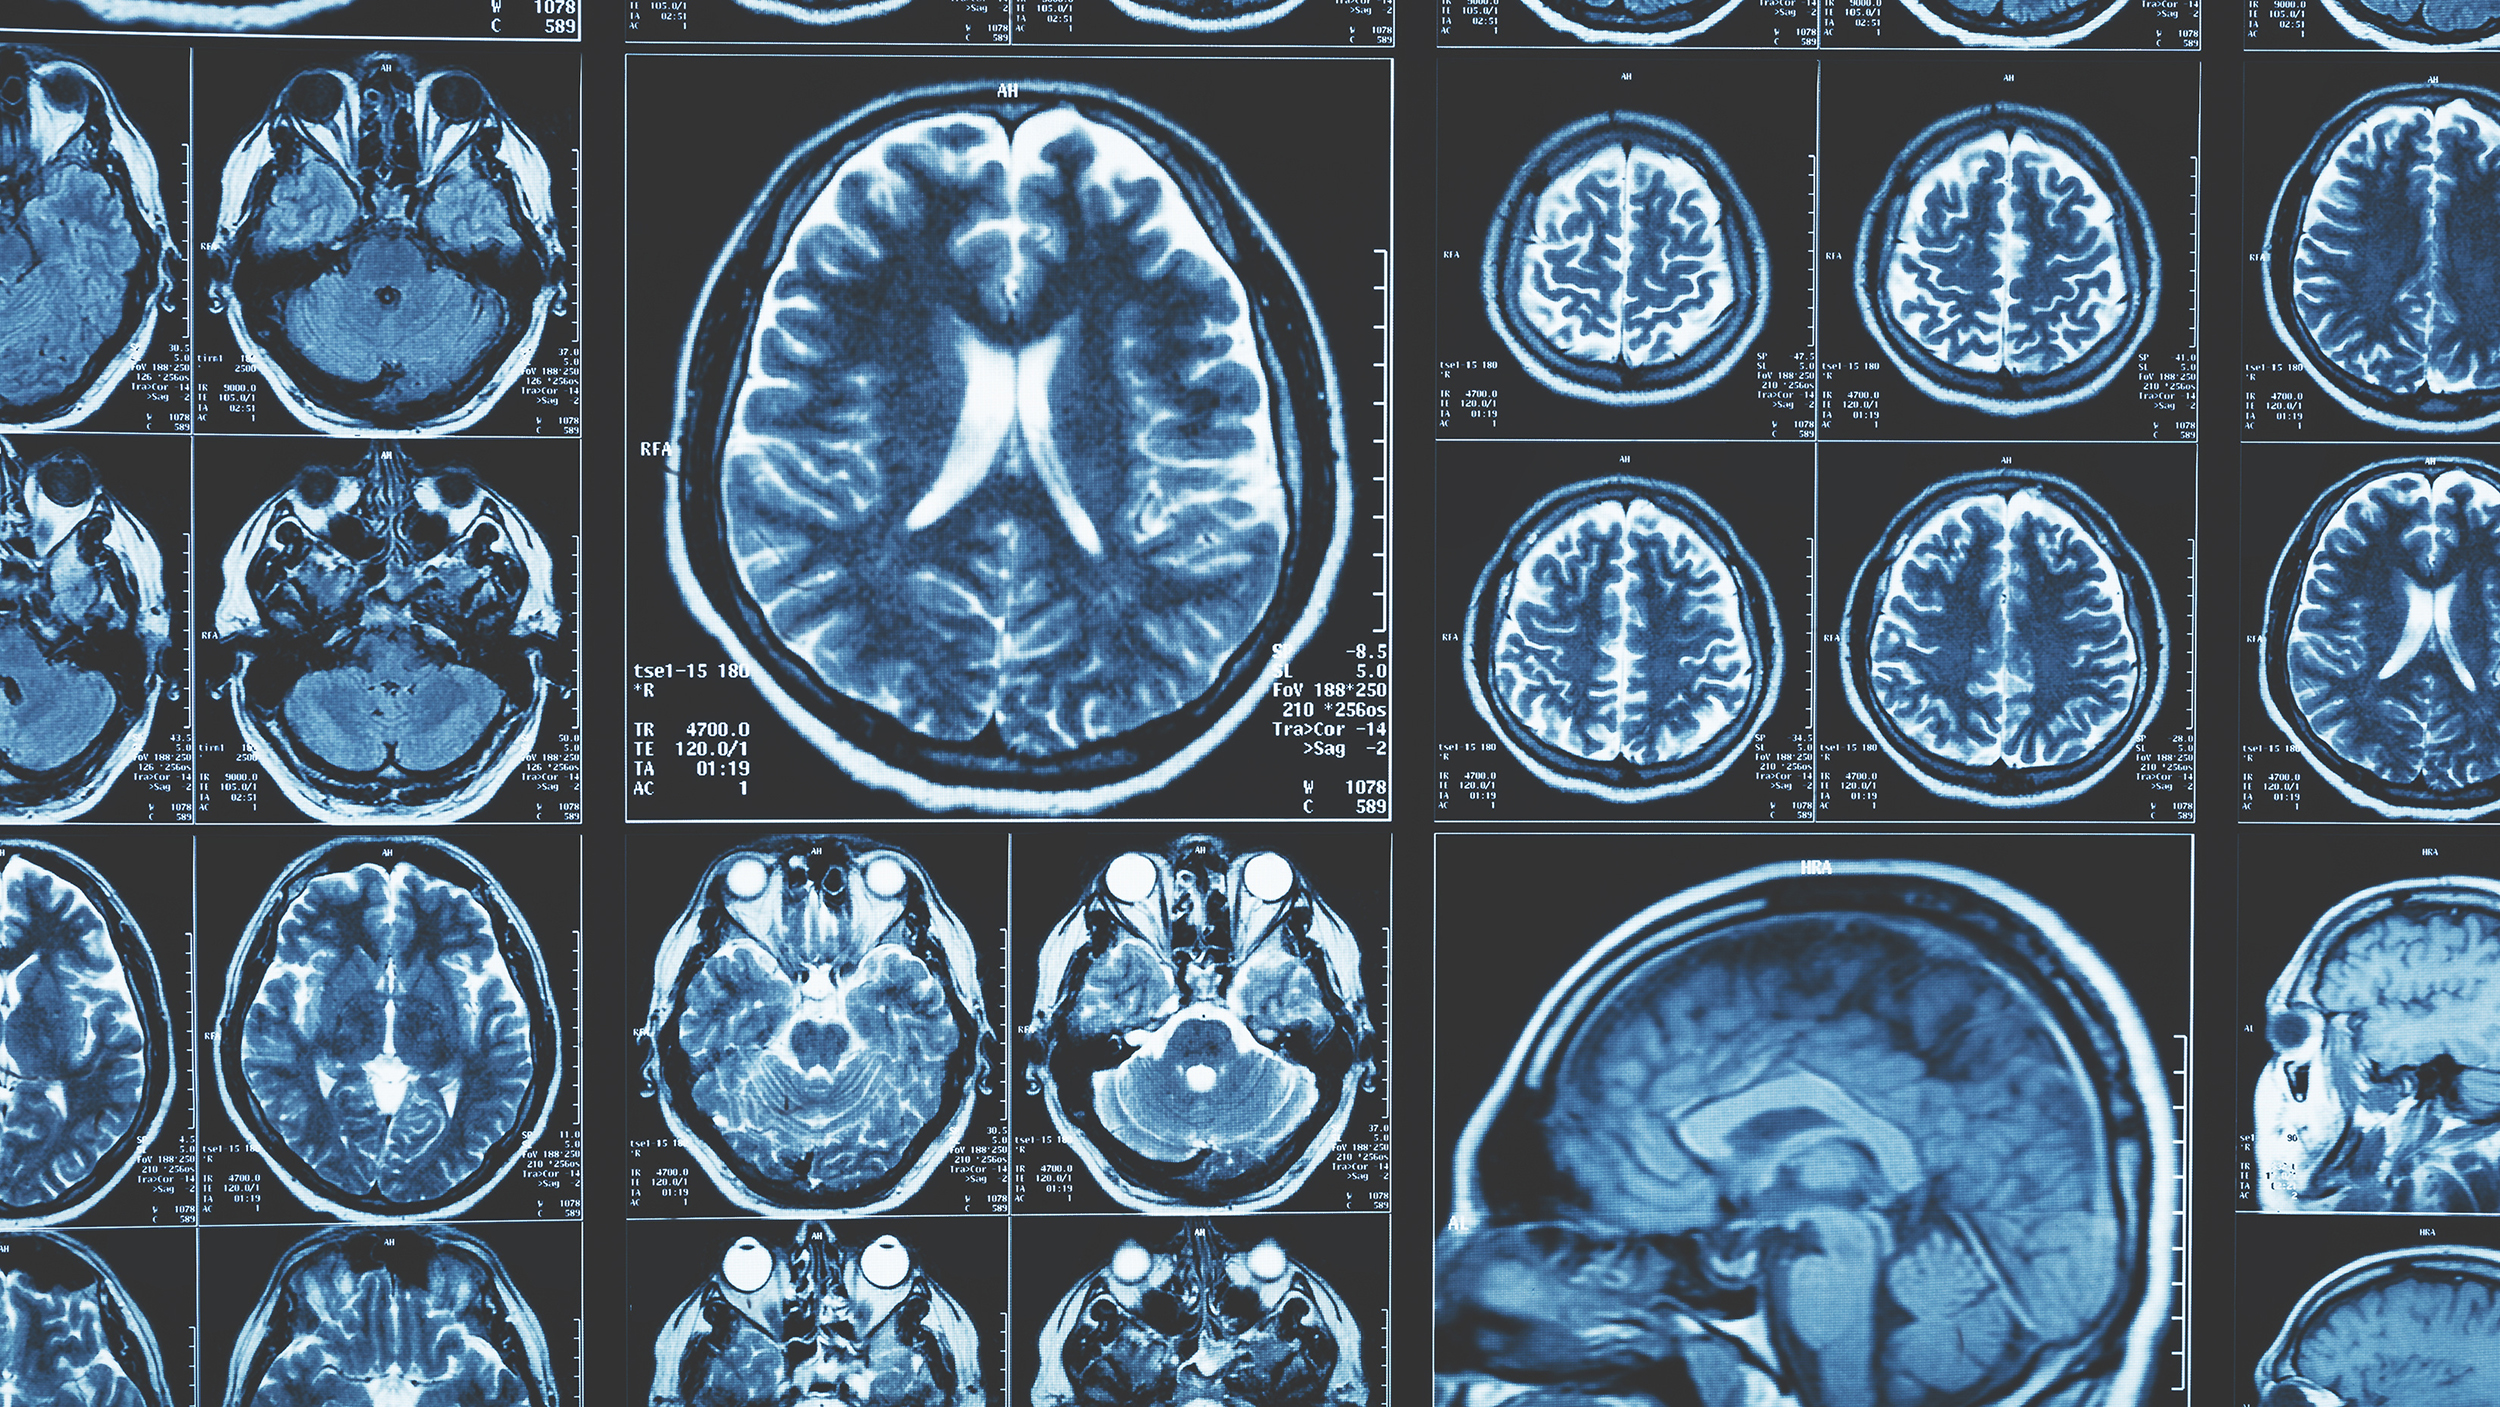

L’ultimo nostro studio ha analizzato sezioni di mesencefalo post mortem di persone con Parkinson e di persone con Alzheimer, utilizzando sequenze di risonanza magnetica (RM) sensibili alla neuromelanina. Le immagini ottenute sono state poi confrontate con misurazioni dirette, effettuate sugli stessi campioni, della quantità di neuromelanina e di ferro.

Rispetto ai soggetti con Alzheimer, le persone con Parkinson presentavano una maggiore concentrazione di ferro nella substantia nigra e aumenti del segnale di risonanza magnetica in alcune regioni del tronco encefalico. Questi dati confermano che la risonanza magnetica sensibile alla neuromelanina è in grado di riflettere in modo attendibile i cambiamenti biologici tipici della malattia.